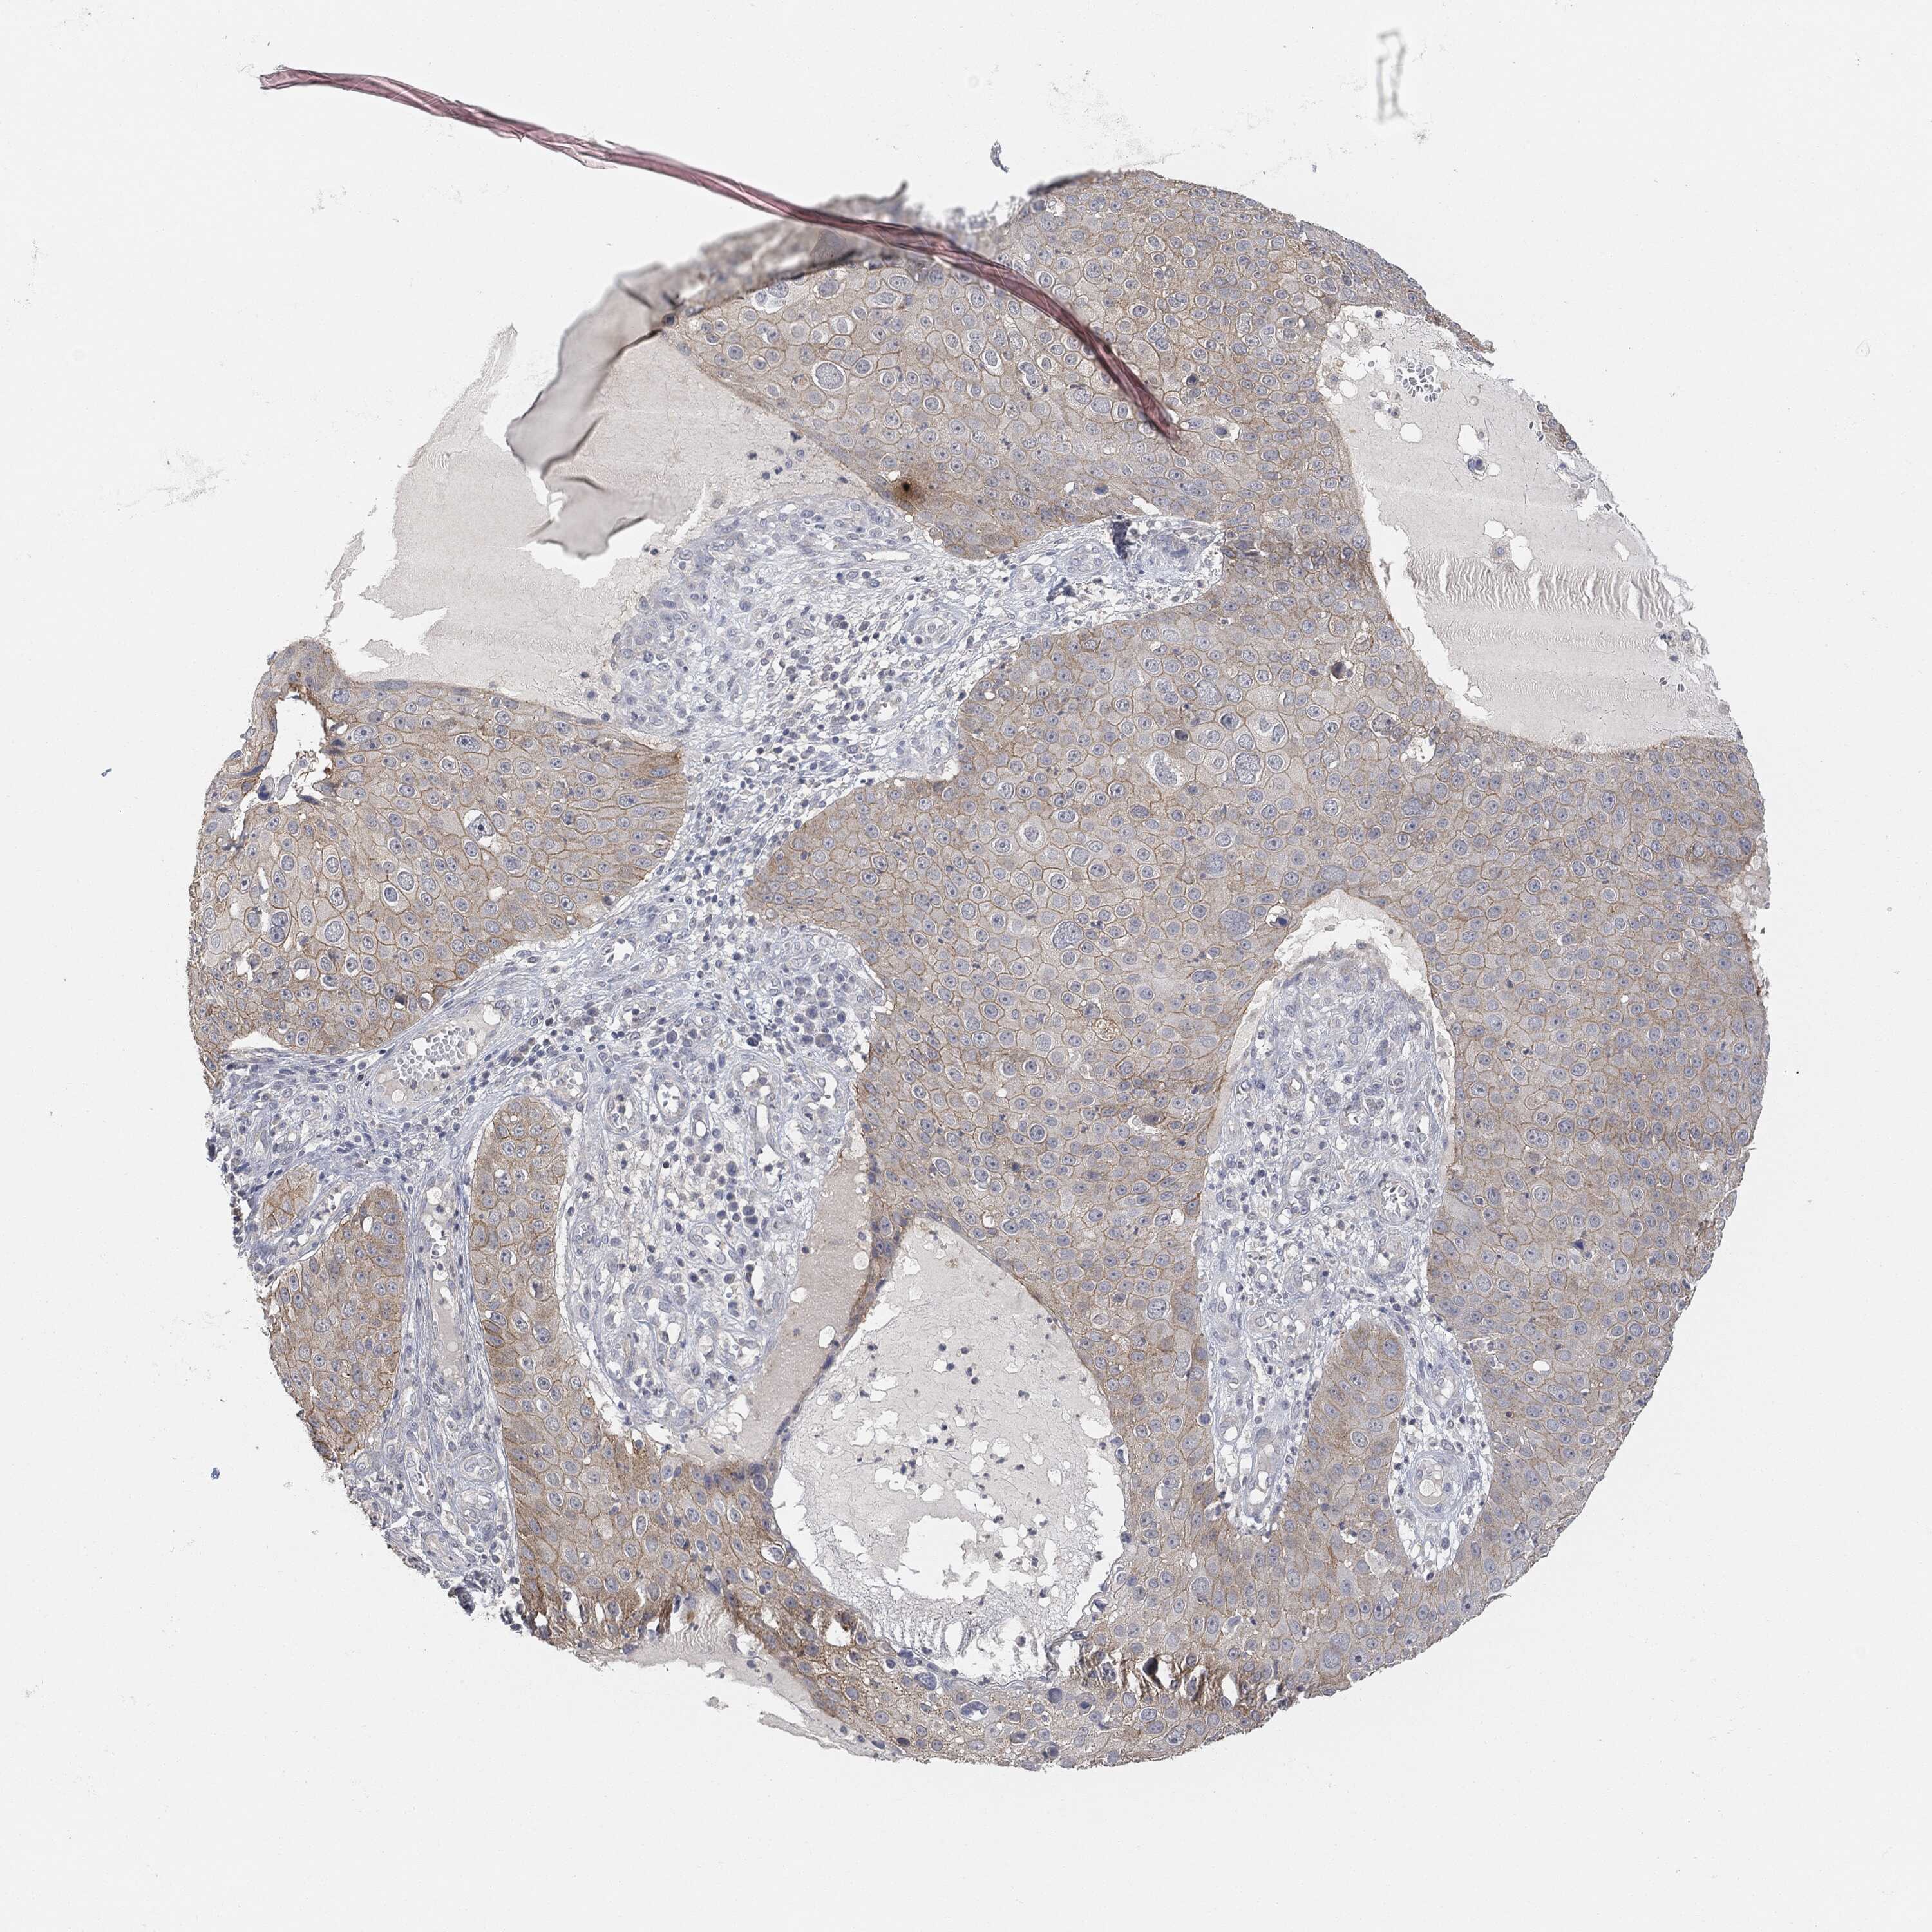

SKIN CANCER - Protein expressioni

A mouse-over function shows sample information and annotation data. Click on an image to view it in a full screen mode. Samples can be filtered based on level of antibody staining by selecting one or several of the following categories: high, medium, low and not detected. The assay and annotation is described here.

Antibody stainingi

Antibody staining in the annotated cell types in the current human tissue is reported as not detected, low, medium, or high, based on conventional immunohistochemistry profiling in selected tissues. This score is based on the combination of the staining intensity and fraction of stained cells.

Each image is clickable and will lead to virtual microscopy that enables deeper exploration of all samples and also displays staining intensity scores, fraction scores and subcellular localization as well as patient and tissue information for each sample.

Squamous cell carcinoma, NOS

Basal cell carcinoma

Squamous cell carcinoma in situ, NOS

Squamous cell carcinoma, metastatic, NOS